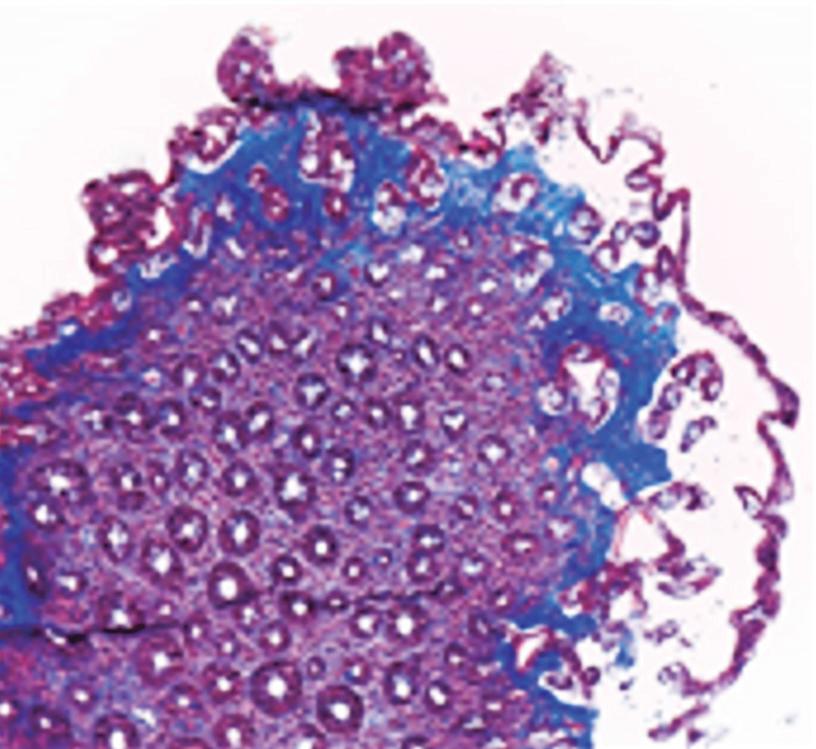

Otra lesión tumoral no dolorosa la constituye la presencia de verrugas genitales (condilomas) producidas por el VPH (virus del papiloma humano). Pueden ser pequeñas o grandes y confluyentes, con un aspecto coliforme de coloración blanquecina. (Figura 2) En estos pacientes es conveniente la investigación de otras enfermedades de transmisión sexual. El estudio con anoscopia de alta resolución facilita la detección de lesiones de alto grado preneoplásicas.4 (Figura 3) El tratamiento de las lesiones del VPH es esencial para prevenir el contagio, la extensión de las lesiones por autoinoculación y la progresión a neoplasias. En este artículo se describen tratamientos tópicos, ablativos y resectivos, como por ejemplo topicación con ácido tricloroacético, imiquimod, electrofulguración, láser o resección quirúrgica.4

Figura 3. Anoscopia de alta resolución 20X. Lesión condilomatosa endoanal de bajo grado sobre la línea pectínea (flecha)